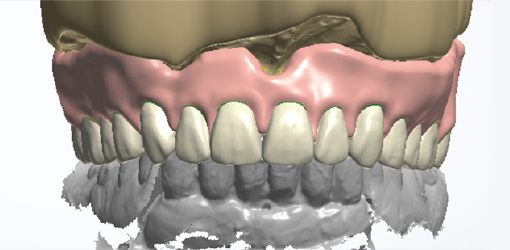

Digital denture production

Digital denture designed from existing dental CAD software (3Shape, exocad, etc.)

Digital denture production

Digital denture designed from existing dental CAD software (3Shape, exocad, etc.)